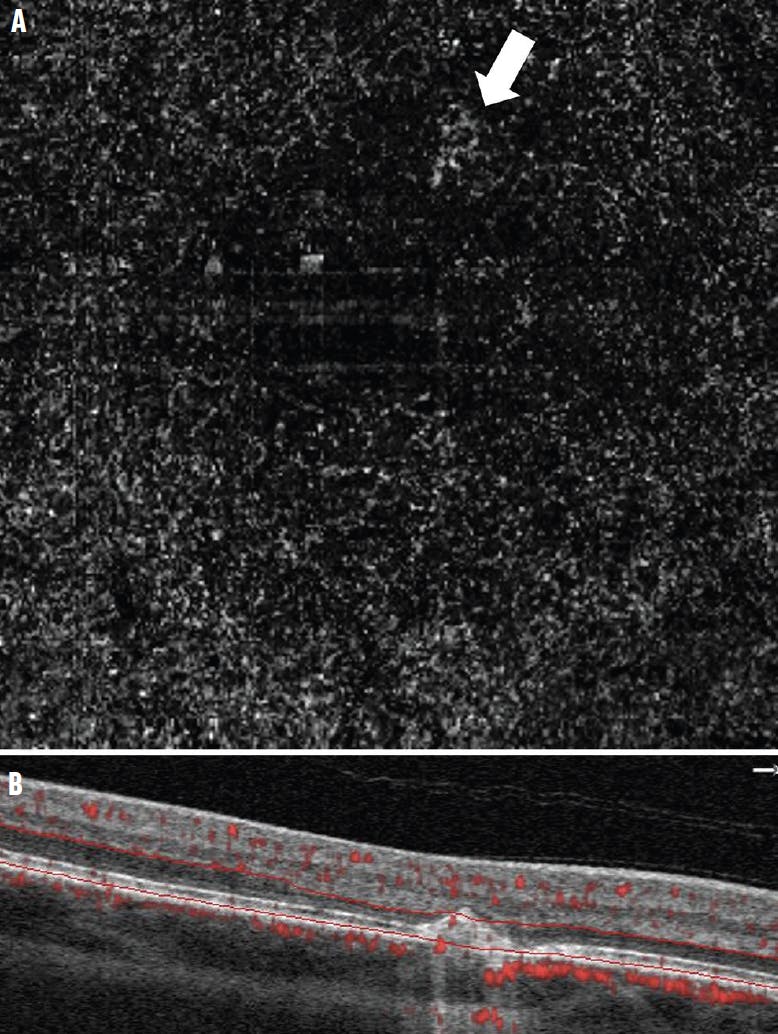

<p>Figure 5. The en face deep capillary plexus slab of the eye of a 77-year-old man with AMD showed a subtle area of possible neovascularization in the outer retinal slab, consistent with possible type 3 neovascularization in AMD (A, arrow). By looking at the cross-section with flow overlay (B), an area of definite abnormal flow with surrounding outer retinal hyperreflectivity confirms the neovascular lesion (circle). The OCT B-scan with flow overlay was useful to confirm the presence of neovascularization due to the poor quality of the en face image. The B-scan can also be helpful in situations where the area of neovascularization may be too small or inconclusive on the en face slab.</p>

Figure 5. The en face deep capillary plexus slab of the eye of a 77-year-old man with AMD showed a subtle area of possible neovascularization in the outer retinal slab, consistent with possible type 3 neovascularization in AMD (A, arrow). By looking at the cross-section with flow overlay (B), an area of definite abnormal flow with surrounding outer retinal hyperreflectivity confirms the neovascular lesion (circle). The OCT B-scan with flow overlay was useful to confirm the presence of neovascularization due to the poor quality of the en face image. The B-scan can also be helpful in situations where the area of neovascularization may be too small or inconclusive on the en face slab.